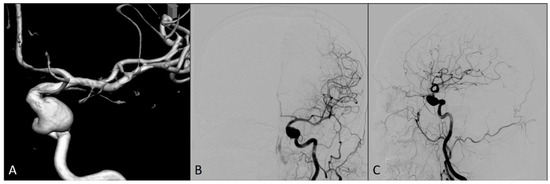

2. Case Report